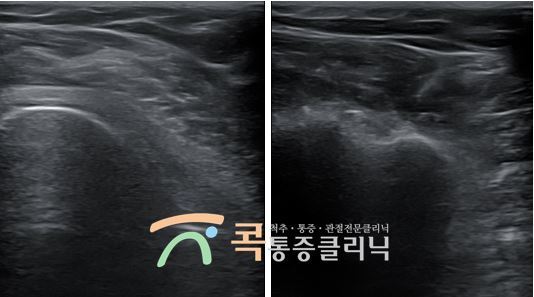

검사 : 초음파 검진

진단 : 회전근개 부분 파열증

치료 : 검진 후 회전근개 부분 파열증이 있으셨고, 수술을 시행할 만큼 질환이 심각한 것은 아니어서 초음파유도하 주사치료 시행

초음파유도하주사치료는 관절 초음파를 어깨관절에 시행하여 정확하게 병변을 치료하게 해주는 가장 기본적인 어깨치료입니다. 실시간으로 초음파 영상을 확인하면서 진단과 동시에 약물을 이용한 주사 치료가 가능한 방법이랍니다. 실제 통증 부위를 세밀하게 보며 신경의 염증을 줄여줄 수 있는 새로운 세포가 빠르게 재생할 수 있도록 도와주는 약물을 주입합니다. 단, 정확한 양의 약물을 정확한 부위에 주입해야 하기 때문에 숙련된 전문의의 치료가 중요한 치료방법이랍니다.